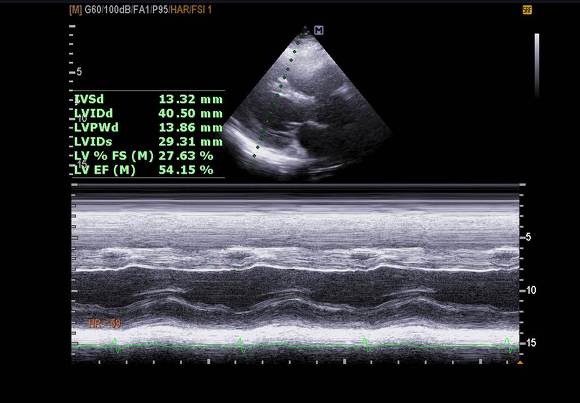

pic 2. PLAX (teich) - wall thickness 13 mm

septum 쪽은 거의 움직임 안보임.

이로 인해  특히 septum 쪽 wall motion 이 떨어져 있었습니다.